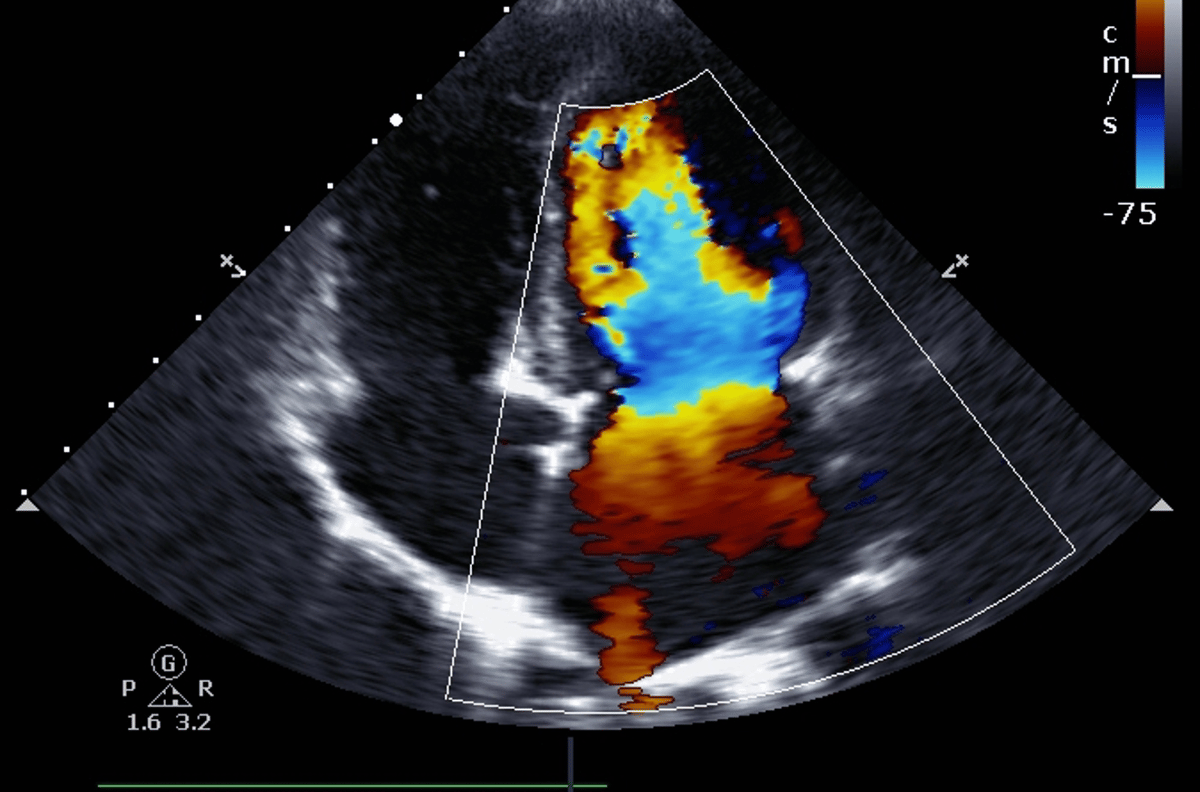

Além disso, realizamos exames laboratoriais e de imagem, incluindo exames de sangue, Doppler, eletrocardiograma, densitometria óssea, mamografia, ecocardiograma, biópsia e ultrassonografias (convencional, 3D e morfológica).

Ultrassom do coração que avalia sua estrutura e funcionamento, identificando problemas cardíacos.

O ecocardiograma é um exame de ultrassom do coração que fornece imagens do órgão.